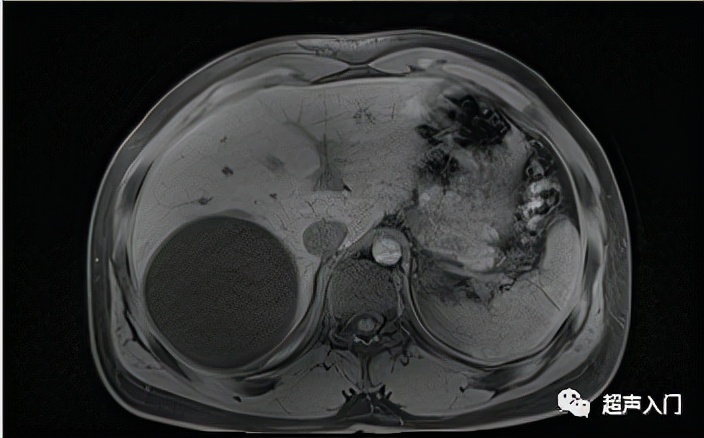

3、混合型

多由于老化和机械、化学损伤以及感染使包虫囊肿出现一系列变性、退化、坏死等改变,超声可显示内囊分离、内囊破裂塌陷、囊实变及实变等改变,呈现高低不等、点状片状回声夹杂的混合回声团块。

实变型(CE4)

图源:人卫出版社教材及课件